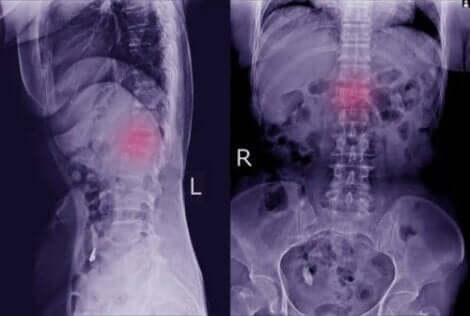

Zdjęcie kręgosłupa

Zdjęcia rentgenowskie są najczęstszą techniką diagnozowania dolegliwości.

Tego typu objawy fizyczne łatwo jest przeoczyć. Jednak gdy je zauważysz warto udać się do lekarza, który po wykonaniu prześwietlenia będzie w stanie zdiagnozować chorobę.

W niektórych przypadkach lekarz może zlecić bardziej szczegółowe badania, takie jak tomografia komputerowa lub rezonans magnetyczny. Dzięki tym dodatkowym testom można zdiagnozować kręgozmyk oraz jego ewentualny wpływ na kości i nerwy.